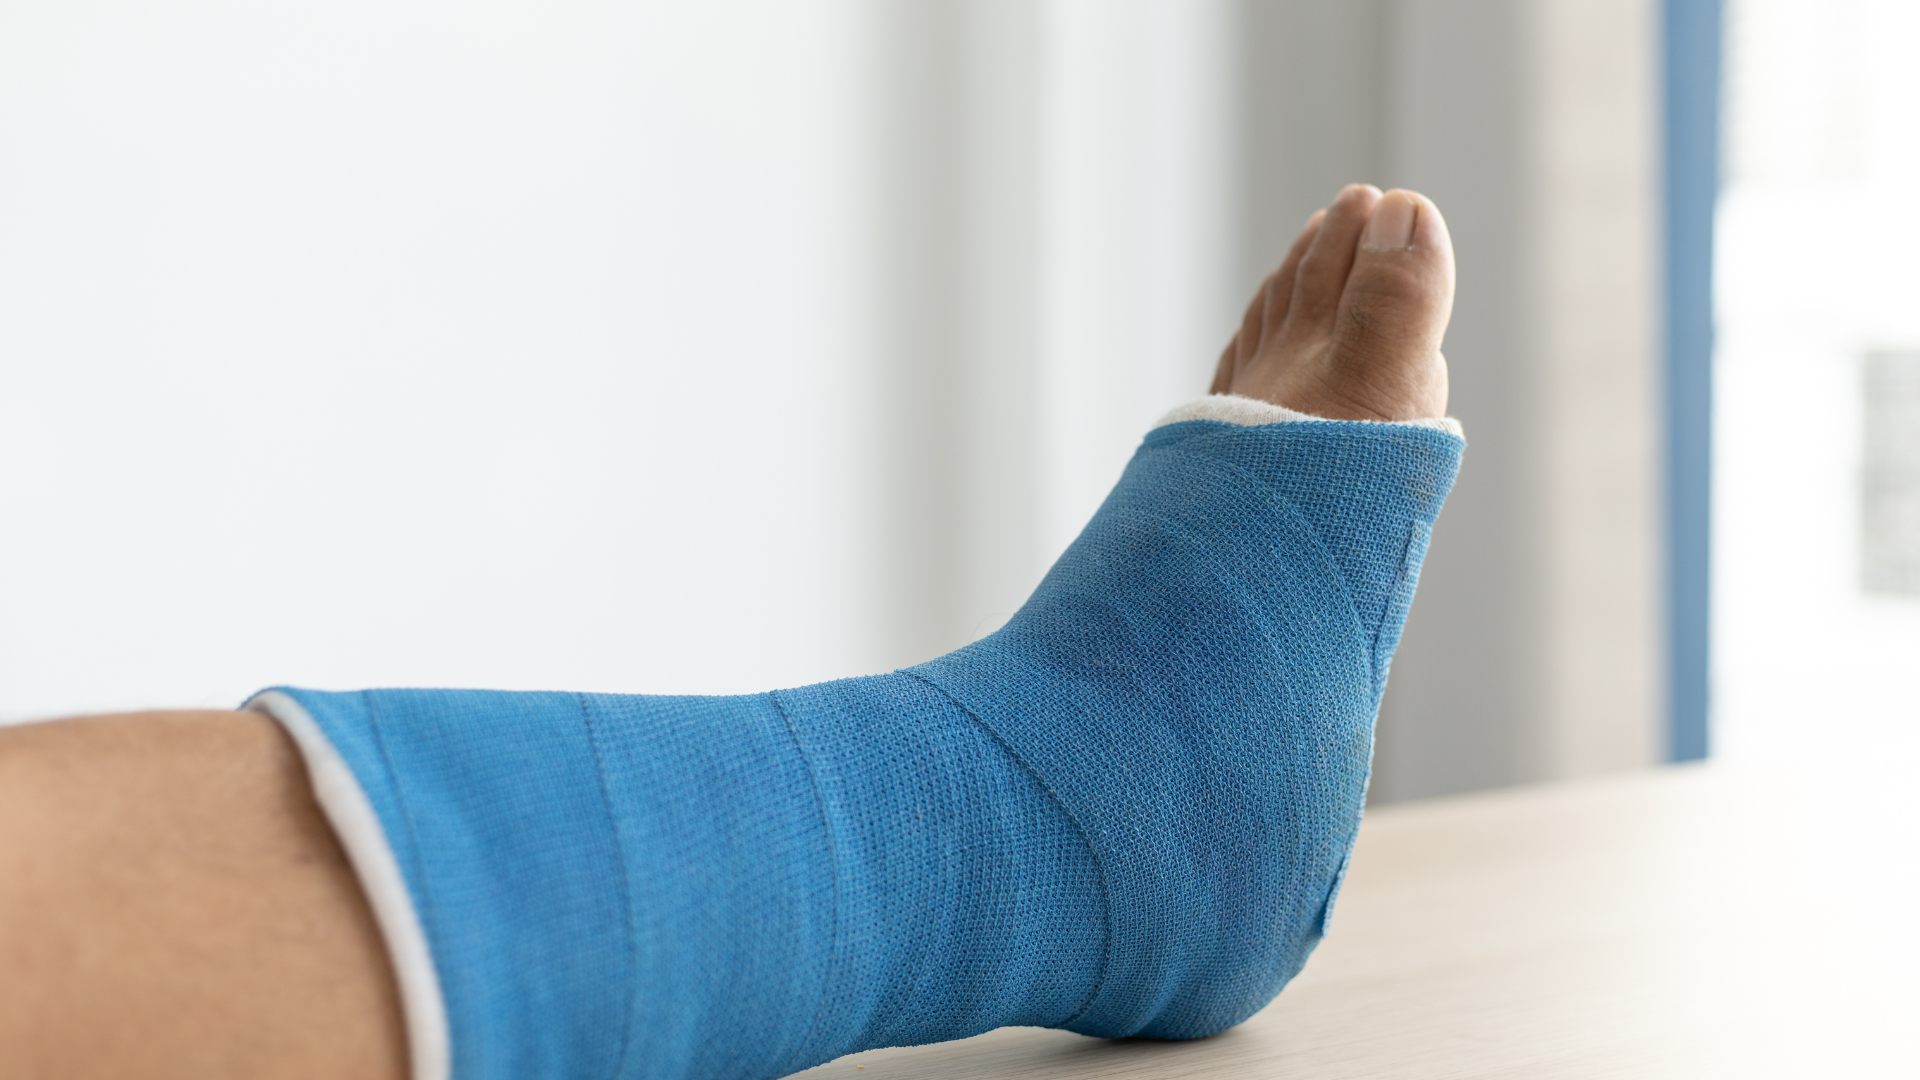

- Bó bột hoặc nẹp: Áp dụng cho các trường hợp gãy kín, ít di lệch. Thời gian bó bột thường kéo dài 4 - 8 tuần.